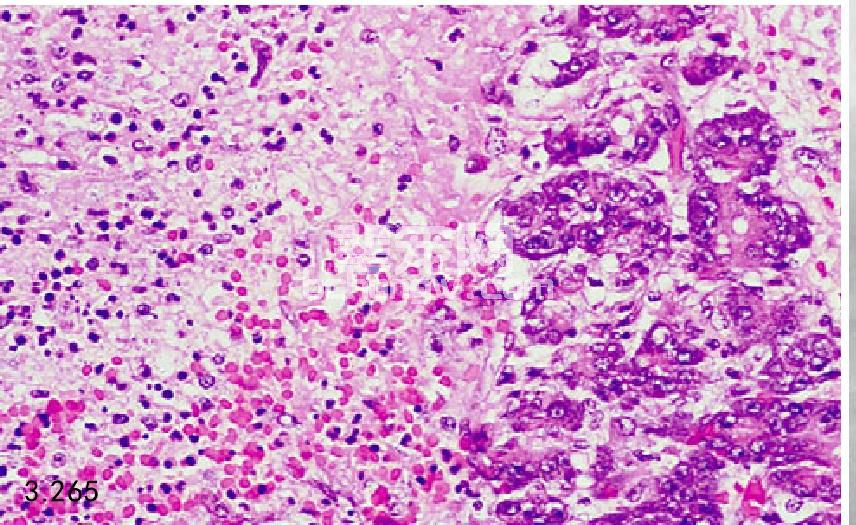

图3.265和图3.266 上图患犬胰腺的组织病理学图片显示为腺体坏死、出血、水肿,由中性粒细胞和巨嗜细胞的炎性浸润(H&E)。